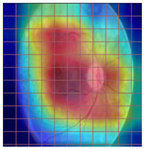

3.2. Models Explainability on the Test Set

| Original Image | VGG16 | ResNet-18 | DenseNet-121 |

|---|---|---|---|

![]() | ![]() | ![]() | ![]() |

| (a) | |||

| (b) | |||

| (c) | |||

| (d) | |||

| Model | Conformity with Normal Retinal Photos | Conformity with Abnormal Retinal Photos | Average Conformity |

| VGG16 | 0.2000 | 0.2414 | 0.2207 |

| ResNet-18 | 0.0294 | 0.0645 | 0.0469 |

| DenseNet-121 | 0.0385 | 0.0286 | 0.0336 |